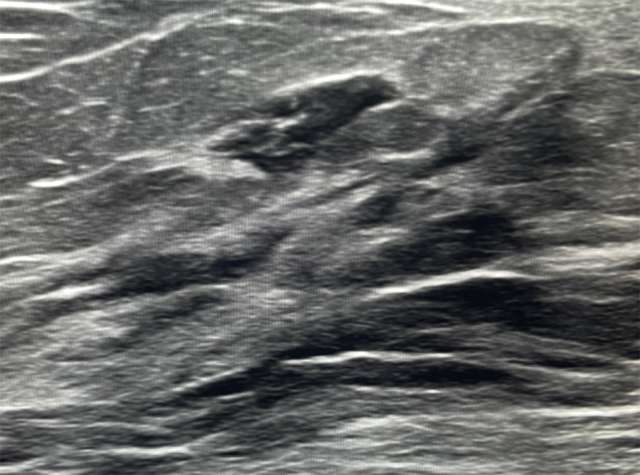

Case: Lymphoma of the Breast Figure 2

Ultrasound demonstrates a vascular oval mass with circumscribed margins that correlates to mammographic finding. Biopsy of this area showed grade 2 follicular lymphoma.